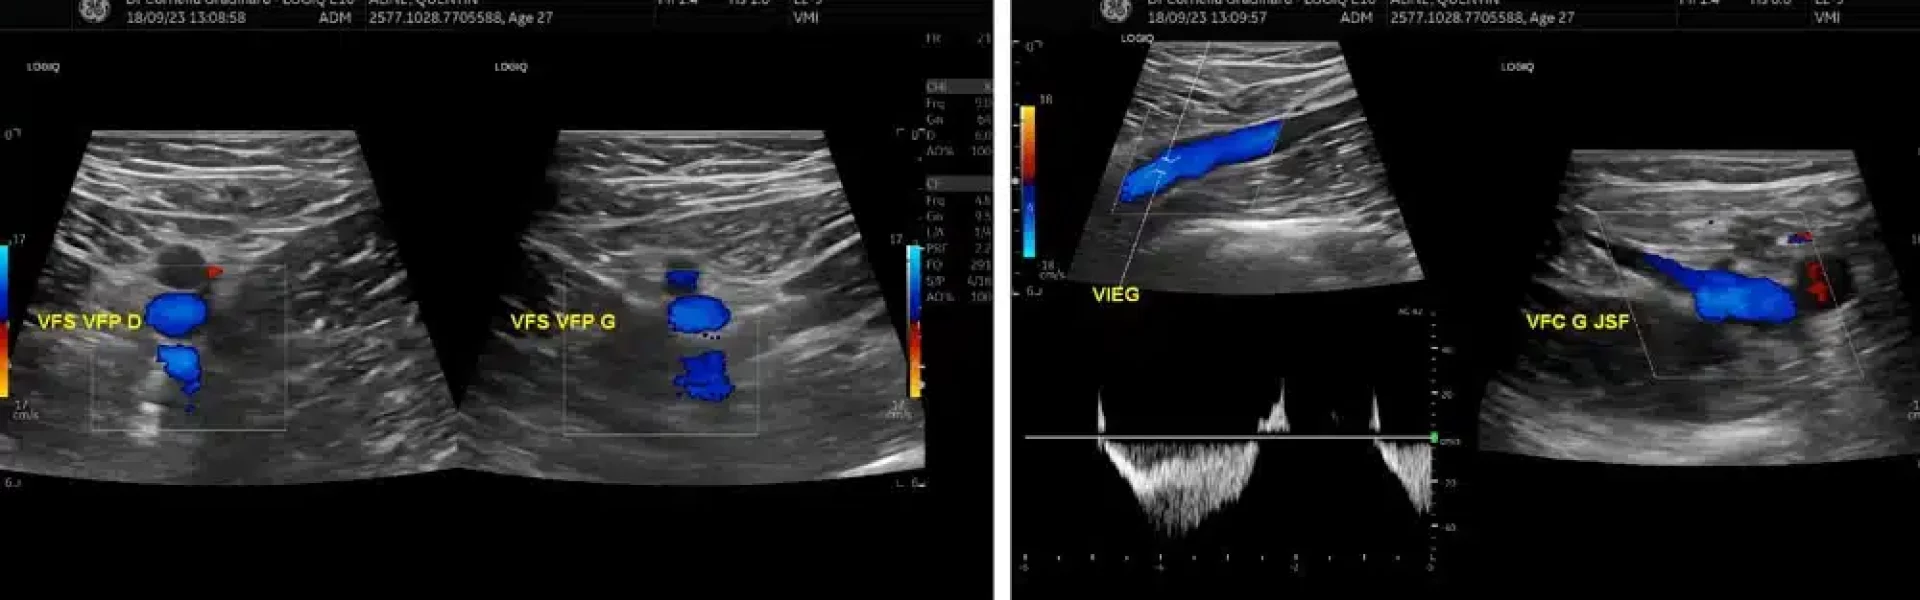

L’écho–doppler veineux des membres inférieurs est une technique d’imagerie médicale utilisant les ultrasons. À l’occasion de cet examen une sonde est placée sur vos membres inférieurs suite à l’application d’un gel à base d’eau, on exerce ensuite une légère pression sur certaines zones afin d’étudier le sens et le mouvement des flux sanguins.

• Cet examen peut mettre en évidence une insuffisance veineuse superficielle et profonde et parfois des varices nécessitant un traitement de celles-ci avant une possible intervention. Dans ce cas particulier il faudra traiter les varices avant l’opération du lipœdème par liposuccion WAL et attendre un minimum de 2 mois entre les deux actes.

• Une phlébite peut être détectée à l’aide de cet examen, notamment à l’occasion de l’échographie doppler post-opératoire recommandée par le Docteur Nicolas Zwillinger. Dans ce cas particulier, un traitement d’anticoagulants sera préconisé, associé à la compression post-opératoire. N’hésitez pas à consulter notre article traitant de ce sujet.

• L’écho doppler peut également détecter un angiome : lésion bénigne du système vasculaire, sans conséquence pour une possible intervention.